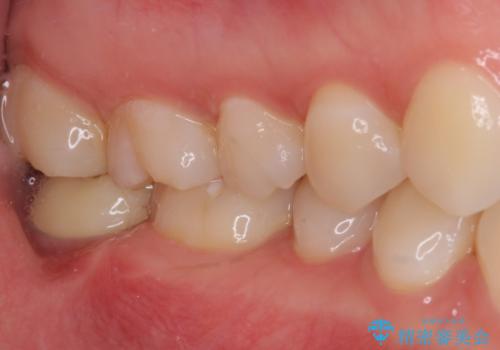

歯の高さが低く、かぶせものを安定して維持させることができないため、歯冠長延長術により歯の高さを増大させた上で、オールセラミッククラウンにて補綴することとしました。

歯の高さが増したことで、かぶせものが外れにくくなったことはもちろん、今まで無理と言われていたセラミッククラウンも装着でき、さらには歯間部の清掃性も向上したため、患者様には大変満足していただけました。